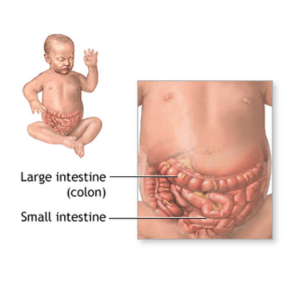

Intestinal obstruction